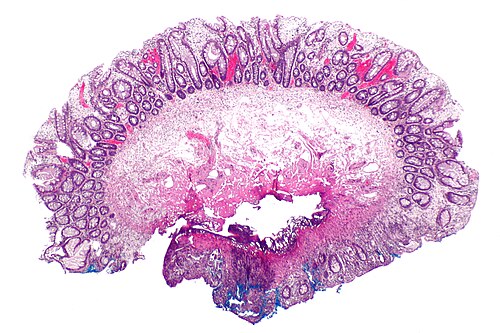

Primary image

Very low magnification. H&E stain.